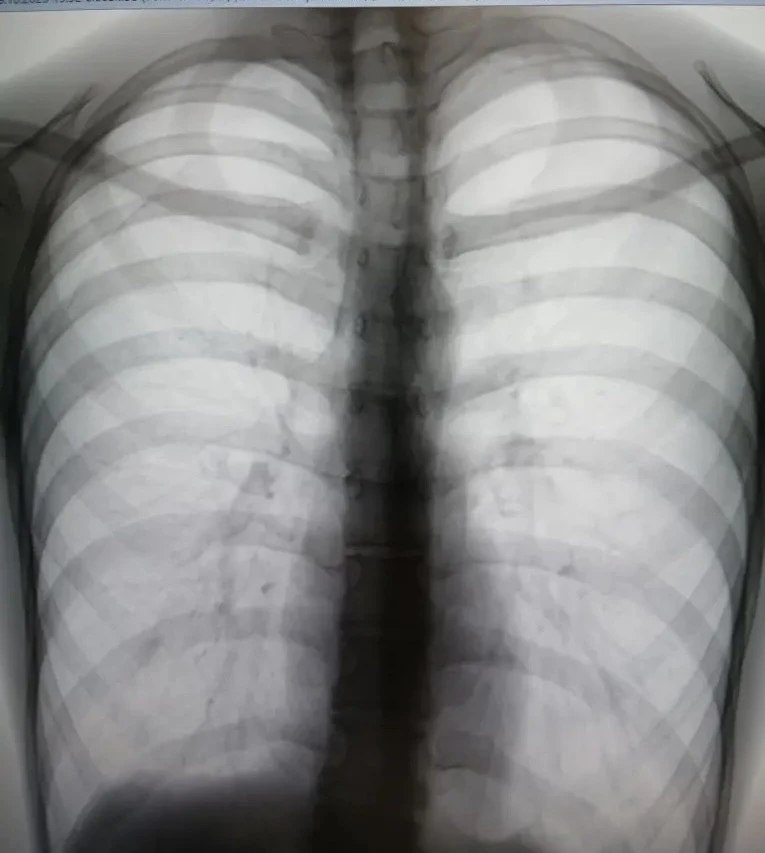

На плановом осмотре в поликлинике № 16 рентгенолог Елена Чувашова заподозрила пневмоторакс (воздух в легком) во время флюорографии. Ситуация критическая — легкое могло сжаться в любой момент.

Пациента экстренно осмотрели, вызвали скорую и за полчаса доставили в областную больницу. Уже вечером того же дня торакальный хирург провел операцию.

Всего 3 часа от снимка до спасения!